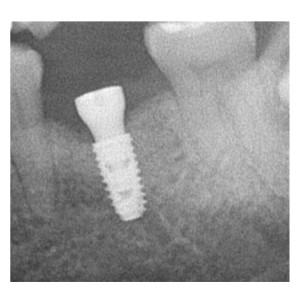

治療途中のインプラント症例

治療途中のインプラント症例です。